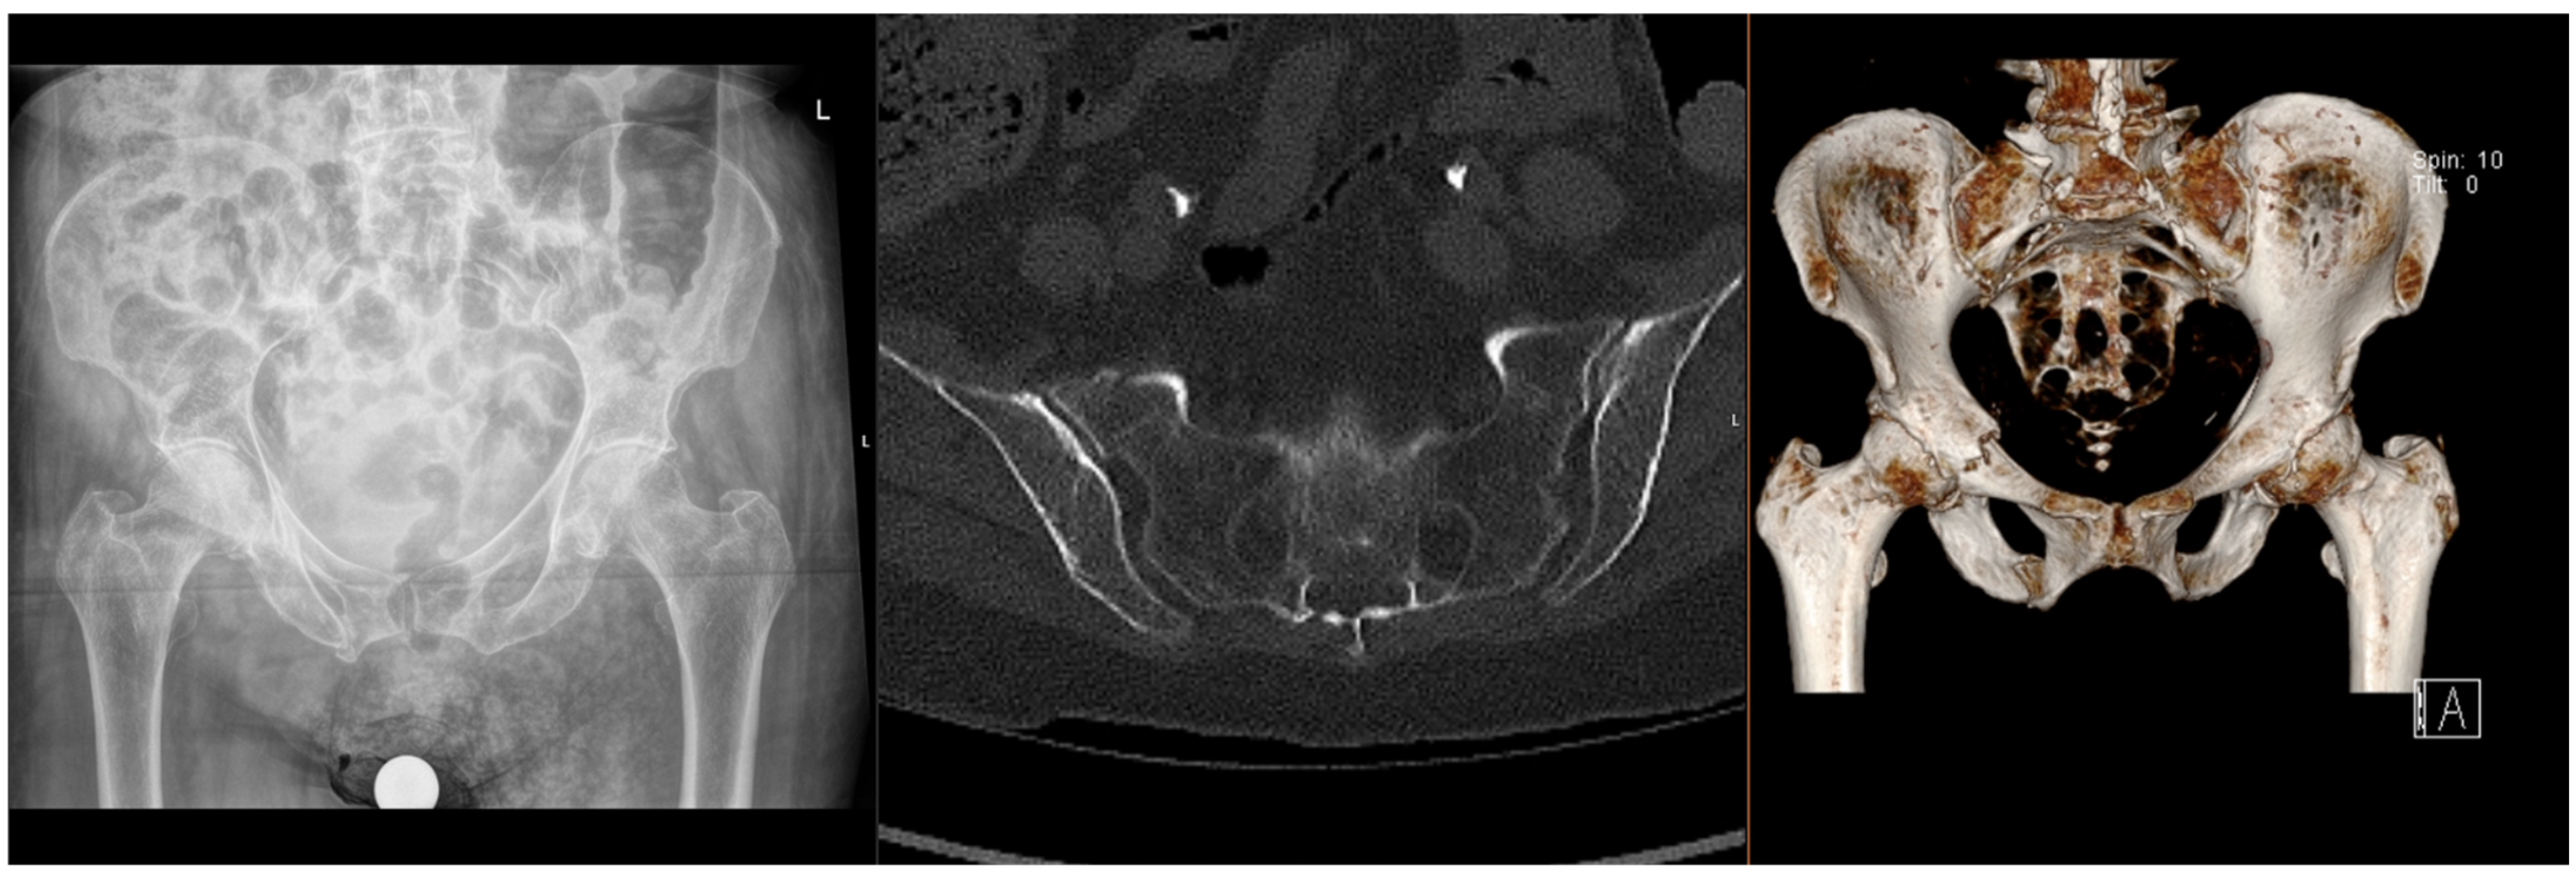

Figure 1.

Radiographs and CT images demonstrating common FFP: lateral compression type.